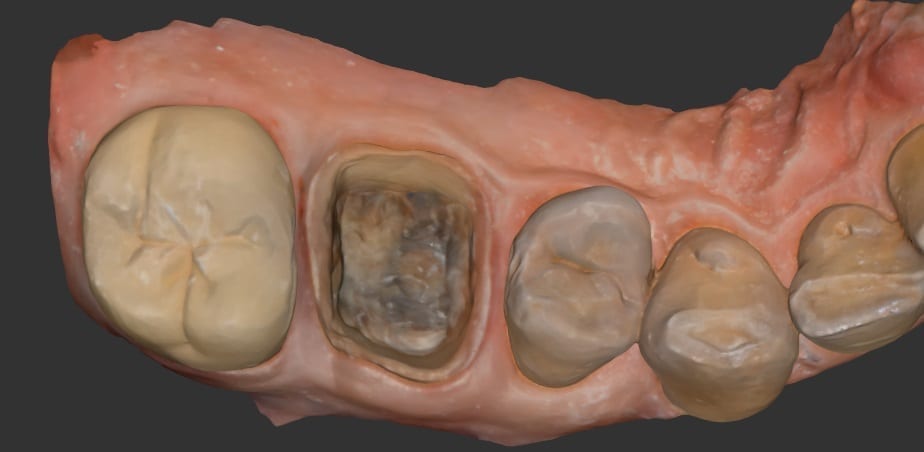

This is an upper and lower case that is scanned with the Medit i500 intra-oral scanner. The lower arch was prepared first and imaged and saved. Then the upper molar was prepared and scanned as well. The bite was captured from the buccal while the patient was biting down in maximum intercuspation. Tissue retraction was not necessary in either case as we could discern the margins simply by the color difference between the tooth structure and the tissue.

Image of case exported as OBJ